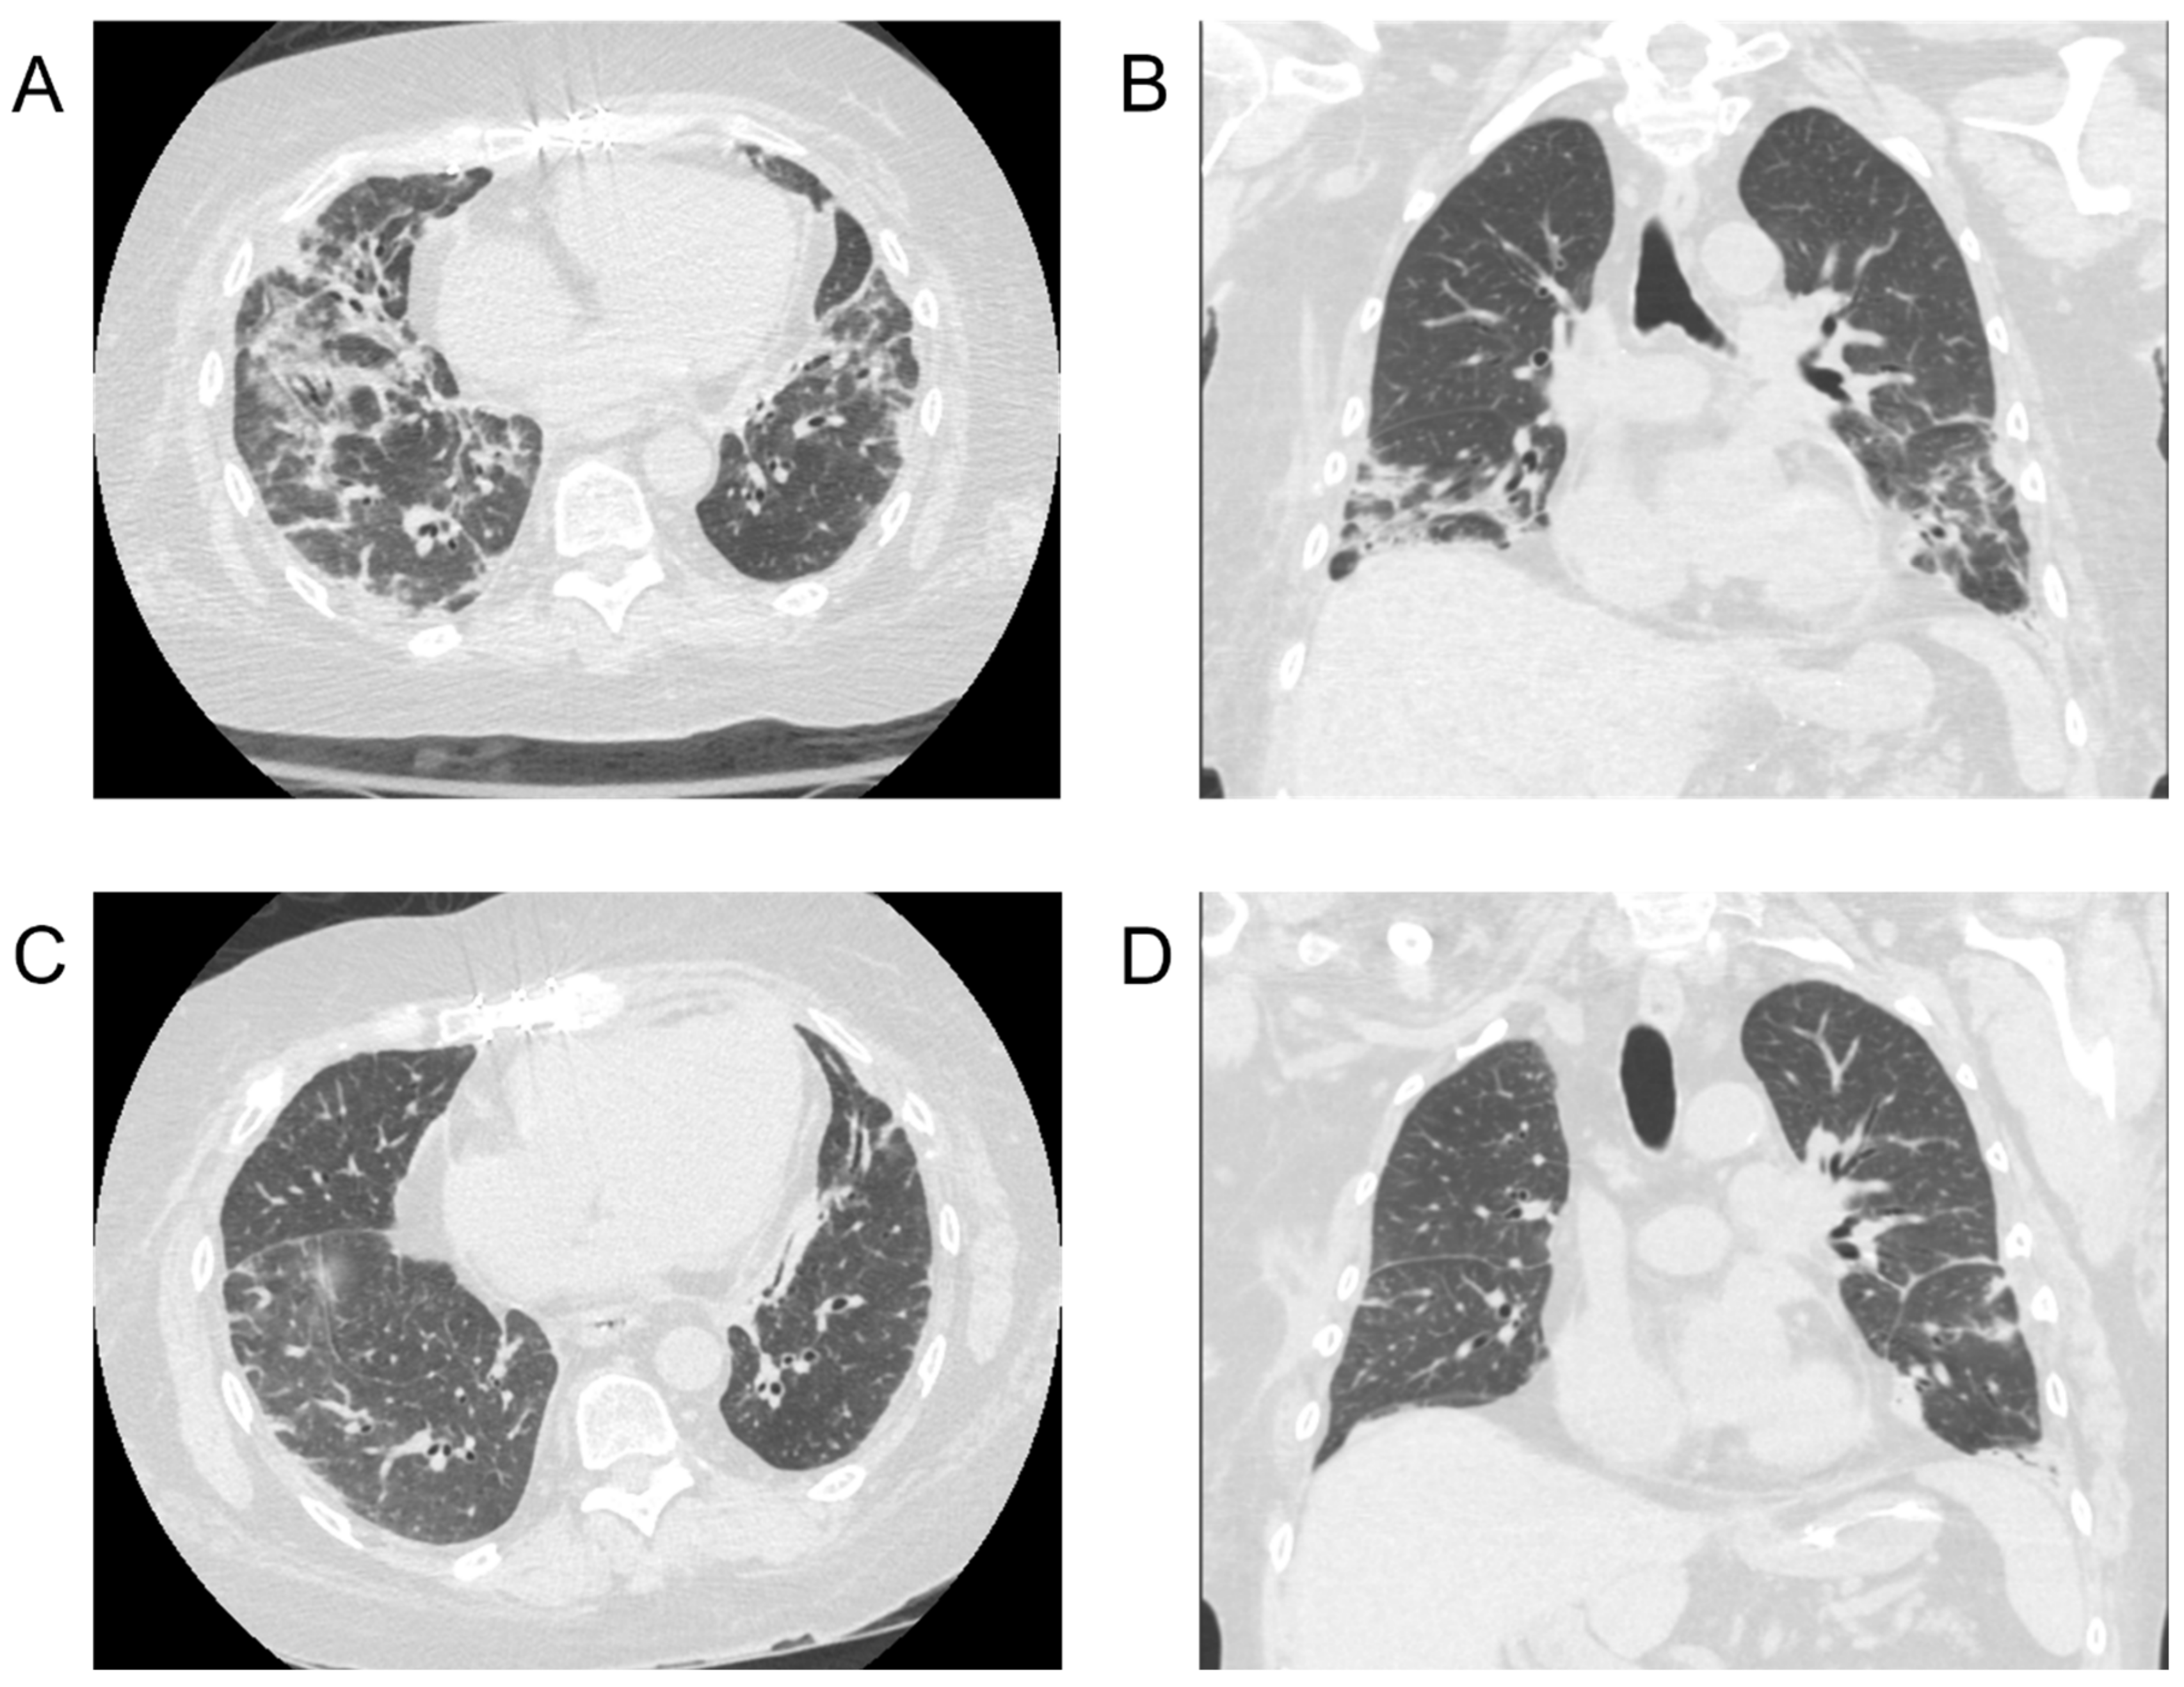

| Zimmermann et al. (2022) [1] | 6 | 60 (38–69) | (4, 2) | IPF (3), IPAF (1), HP (1), Sarcoidosis (1) | NR (4), 18, 22 | HF (3), PHTN (3), HTN (2), PVD (1), CHD (1), Afib (1) | Fatigue (6), Dyspnea (5), Cough (5), Diarrhea (4), Fever (3), Asthenia (3), Nausea (2), Expectoration (2), Headache (2), Myalgia (1), Abdominal Pain (1) | Nasopharyngeal and Oropharyngeal Swab | CT | GGO (6), Consolidation (4), Intersitial Abnormalities (4), Pleural Effusion (3) | 50 (25–122) | 4/4 (100), 1/2 * (50) |

| Myers et al. (2020) [2] | 8 | 60.8 (43–75) | (1, 7) | IPF (5), COPD (2), CF (1) | NR (6), 7, 14 | Prior Smoker (7), Afib (3), CKD (3), DM2 (3), HL (3), DVT (2), HTN (2), CHF (1), CAD (1), OSA (1) | Cough (6), Dyspnea (6), Fever (4), Nausea (3), Fatigue (3) | NR | CT | GGO, Consolidation | 8.6 (2–16) | 6/6 (100), 0/2 * (0) |

| Athanazio et al. (2020) [6] | 1 | 37 | (0, 1) | CF | 13 | None | Dyspnea | Nasopharyngeal Swab | CT | GGO, Consolidation, Pleural Effusion | 39 | 1/1 (100) |

| Keller et al. (2020) [3] | 1 | 69 | (1, 0) | IPF | 8 | GERD, HL, Psoriasis | NR | Nasopharyngeal Swab | CXR, CT | GGO, Consolidation | NR | 1/1 (100) |